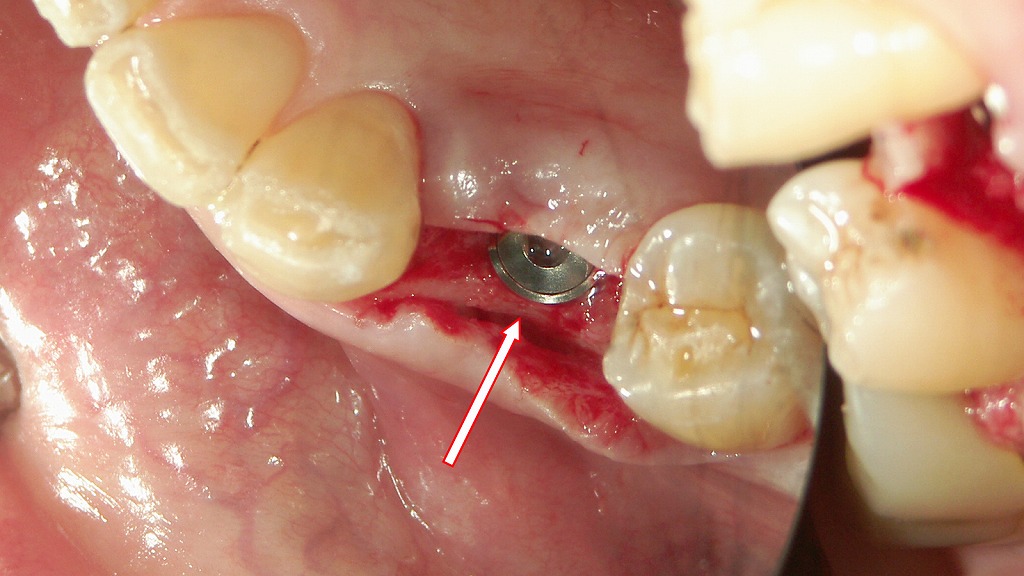

この写真は、下顎右側第1小臼歯(4番)部にインプラントを埋入した直後の術中写真です。矢印の先に見えている金属部分が、**インプラントフィクスチャー(人工歯根)**の上面です。

🔍 解説

■ 手術部位

- 位置:下顎右側4番(第1小臼歯)相当部

- 目的:失われた歯を補うためのインプラント体埋入

■ 見えている構造

- 中央の金属部(矢印):

インプラント本体の上部です。

この部分には後日、アバットメント(支台)や人工歯(上部構造)が接続されます。 - 周囲の歯肉切開部:

手術により粘膜・骨膜を剥離し、骨面が露出しています。

インプラント体が適切な深さに埋入されていることが確認できます。 - 隣在歯(3番・5番):

支持骨や隣接面との距離が確保されており、位置関係は良好です。

■ 状態のポイント

- 歯槽骨内に垂直にフィクスチャーが固定されており、

歯軸方向と平行に設置されているのが分かります。 - 出血は少なく、術野は清潔で視野確保が良好です。

- この段階ではまだ縫合前で、ヒーリングキャップも装着されていません。

🦷 今後の流れ(一般的な工程)

- 埋入後、約2〜3か月の骨結合(オッセオインテグレーション)期間をおく。

- 結合が確認された後、2次手術でアバットメントを装着。

- 歯肉治癒後に人工歯(クラウン)を装着して噛み合わせを回復。